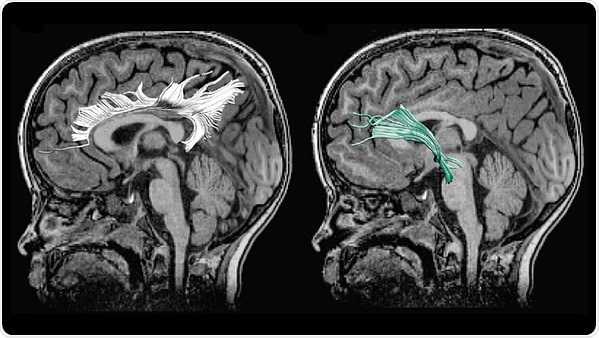

Hay et al. studied 54 mother/child pairs. Mothers answered a survey about their depression symptoms at several points during their pregnancy. The research team employed diffusion MRI, an imaging technique that reveals the strength of structural connections between brain regions, to examine the children’s white matter.

Greater prenatal depression symptoms were associated with weaker white matter connections between brain regions involved in emotional processing. This change could lead to dysregulated emotional states in the children and may explain why the children of depressed mothers have a higher risk of developing depression themselves. The weakened white matter was associated with increased aggression and hyperactivity in the male children. These findings highlight the need for better prenatal care to recognize and treat prenatal depression in order to support the mother and the child’s development.